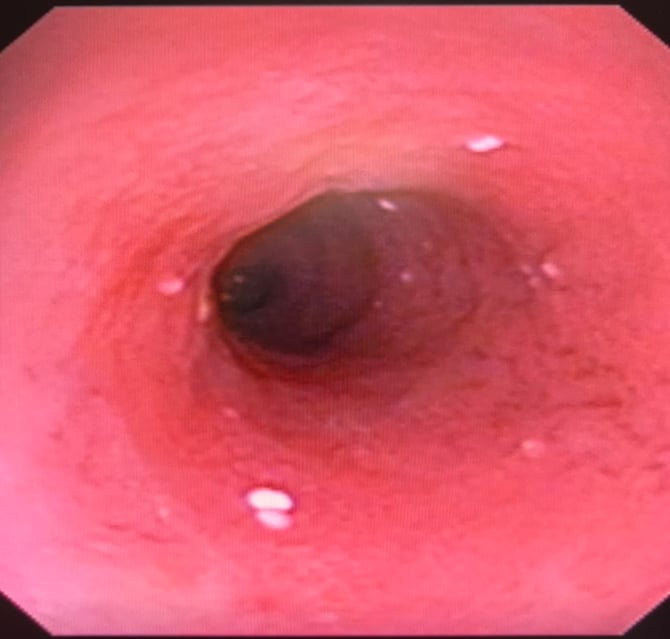

図2

第1076 病日、内視鏡生検を実施し、

十二指腸粘膜のリンパ管拡張および不整が認められた